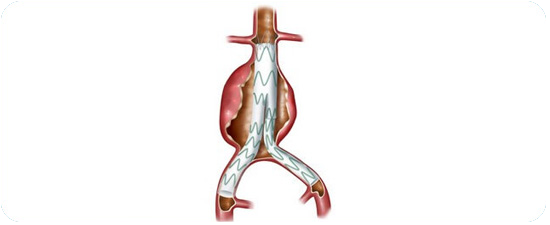

A weak division of the artery or heart wall is replaced with a patch or graft to repair a balloon-like bulge in the artery or wall of the heart muscle.

In addition to these surgeries, a minimally invasive substitute to open-heart surgery that is becoming more common is trans-catheter structural heart surgery. This encompasses guiding a long, thin, flexible tube called a catheter to your heart through blood vessels that can be gained access to from the groin, thigh, abdomen, chest, and neck or collar bone. A small incision is required. This type of surgery includes trans-catheter aortic valve implantation to substitute a faulty aortic valve with a valve made from animal tissue.